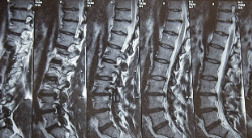

허리디스크란 척추 디스크가 손상되어 디스크 안의 젤과 같은 물질이 디스크 밖으로 살출되어 신경에 압력을 가해 통증을 유발하는 질환입니다. 허리디스크는 허리 부분에서 가장 흔하게 발생하며, 통증뿐만 아니라 산후 조기노화, 척추 굴곡 이상 등의 합병증을 유발할 수 있습니다. 보존적 치료, 약물 치료, 물리치료, 수술 등의 치료 방법이 있으며, 증상과 소견에 따라 적절한 치료가 필요합니다.

허리디스크는 척추 디스크의 손상으로 인해 디스크 안의 젤과 같은 물질이 디스크 밖으로 살출되어 신경에 압력을 가해 통증을 유발하는 질환입니다. 허리디스크는 다양한 증상을 유발할 수 있으며, 그 중에서도 흔히 나타나는 증상은 다음과 같습니다.